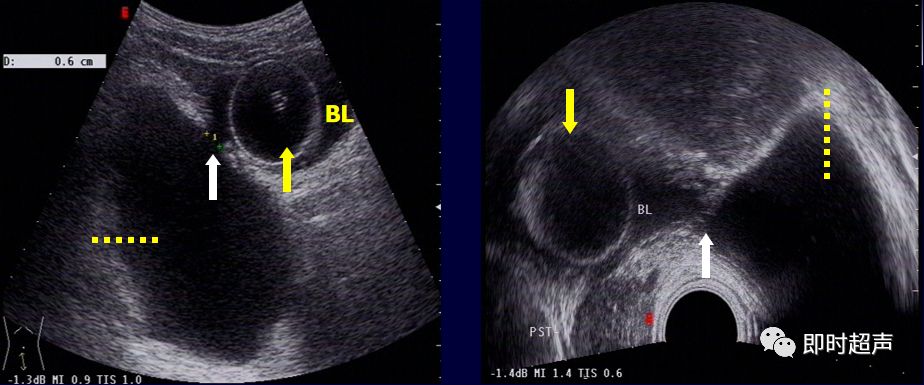

常见膀胱病变的超声表现多图详解

图片尺寸1080x810